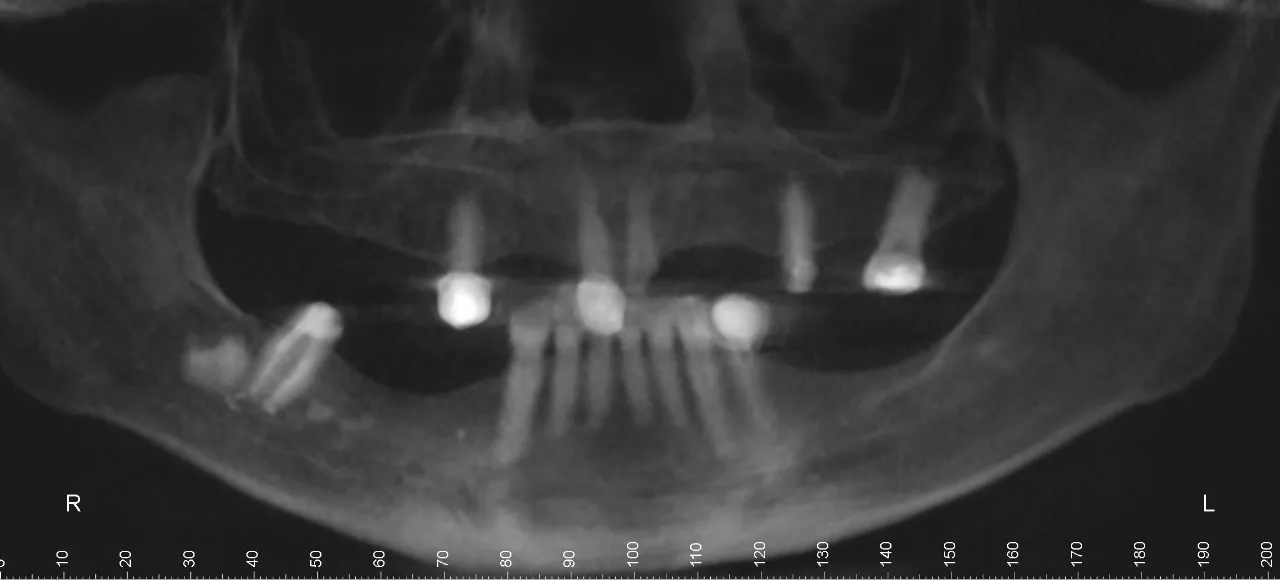

Diagnostic Method

- Remote evaluation of dental scans and photos

- Virtual consultation to discuss treatment expectations and outcomes

- Onsite clinical assessment before finalizing the treatment plan

- Partial edentulism (multiple missing teeth)

- Generalized chronic periodontitis